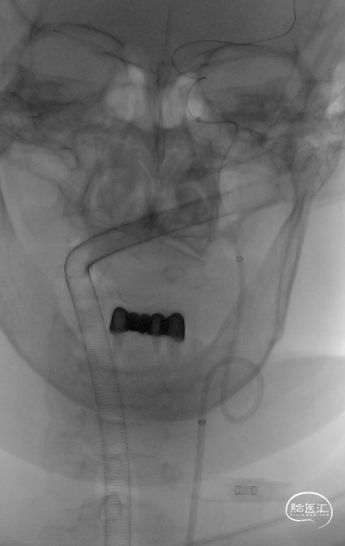

双C造影,确认Pipeline™ Flex血流导向密网支架头端位置。

双C透视,Pipeline™ Flex血流导向密网支架打开。

双C正侧位。

确认通路无夹层、血栓。